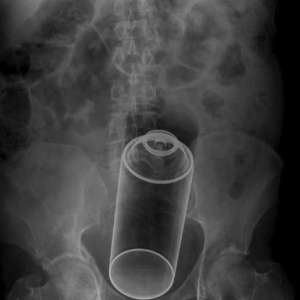

21-летний фрилансер из Ленобласти лишился прямой кишки и теперь будет жить с калоприёмником после неудачного эксперимента «для поднятия настроения».

Врачам дизайнер рассказал: заскучал, решил развлечься, засунул себе в очко дезодорант. Веселее не стало — попытался вытащить, не получилось. Оставил там. Проходил с баллоном в себе три дня, сильно заболело, вызвал скорую.

Прибывшие врачи госпитализировали его с необратимым некрозом тканей. Прямую кишку пришлось ампутировать и теперь сверхразум будет жить с калоприёмником.